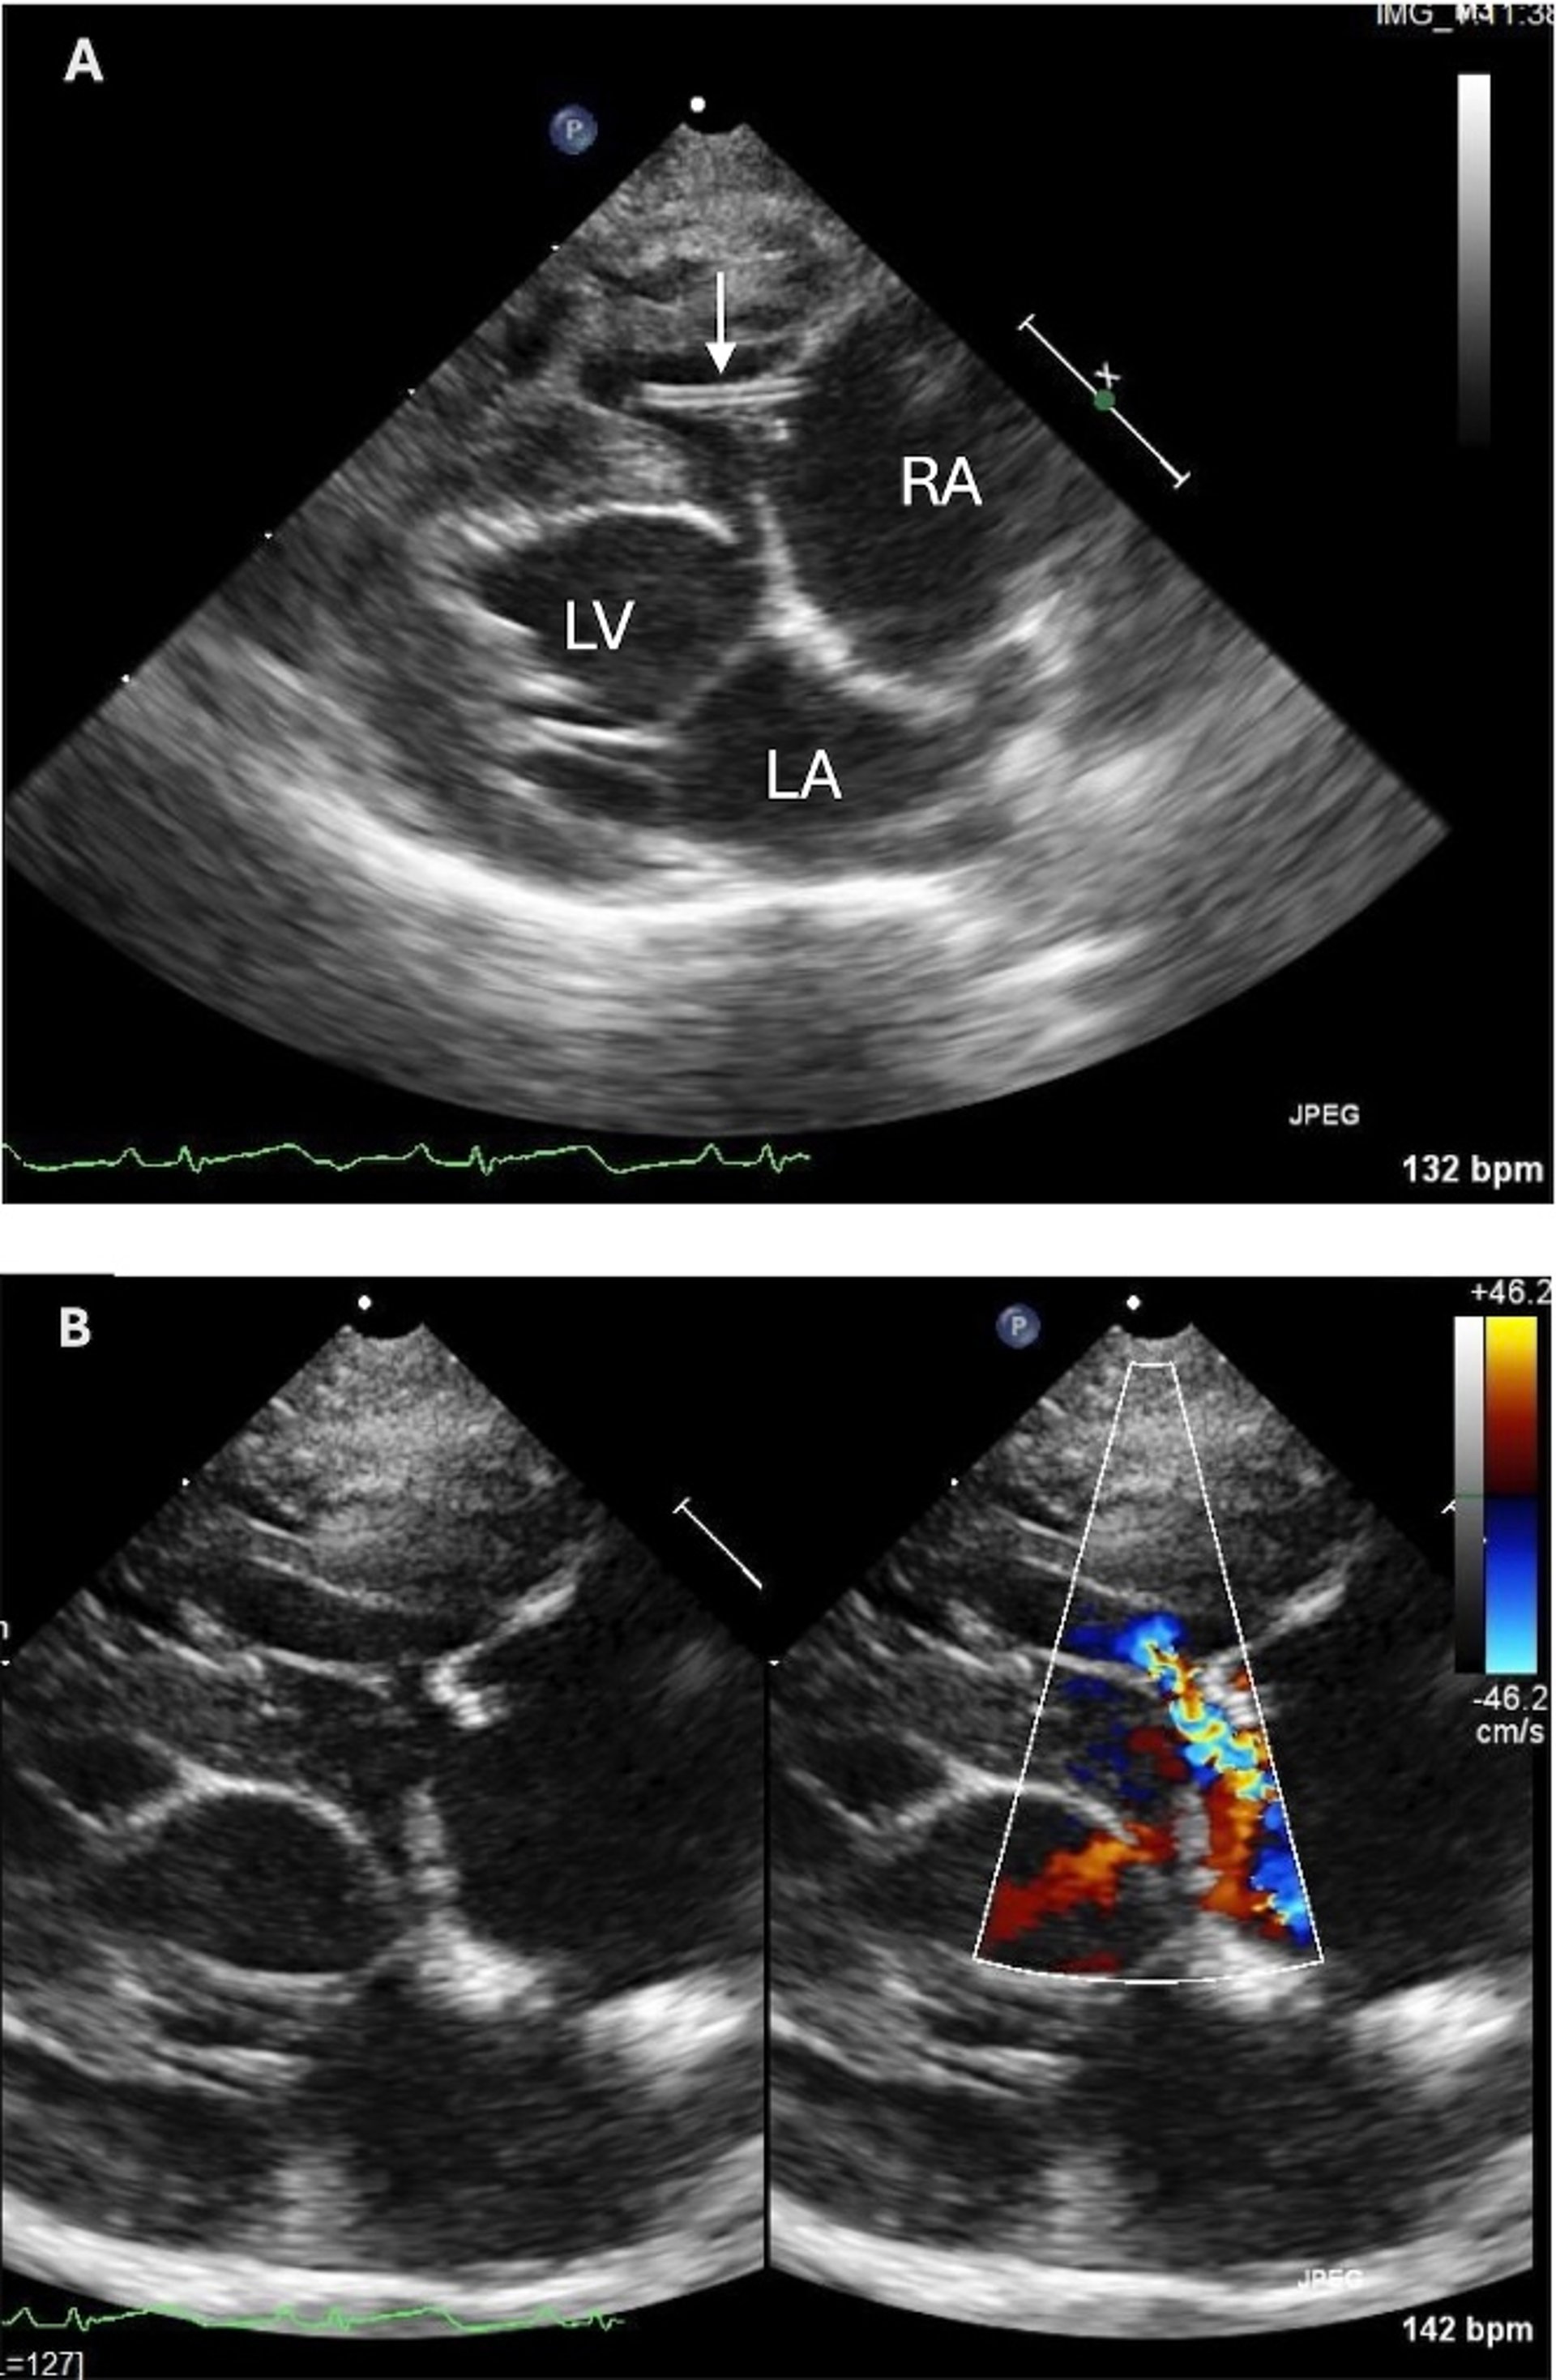

Mature heartworm infection, echocardiogram, cat

Right parasternal 4-chamber echocardiographic view (A) and the same view with color over the tricuspid valve (B) from a 7-year-old spayed female cat with a history of intermittent respiratory distress and syncope in which heartworm antigen and antibody test results were negative. Note the heartworm (hyperechoic parallel lines; arrow) crossing the tricuspid valve. There is mild prolapse of the parietal leaflet of the tricuspid valve leading to mild tricuspid insufficiency. The right atrium is dilated. LA, left atrium; LV, left ventricle; RA, right atrium.

Courtesy of Dr. Marisa K. Ames.